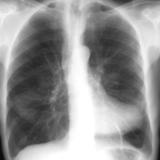

Normal pericardium